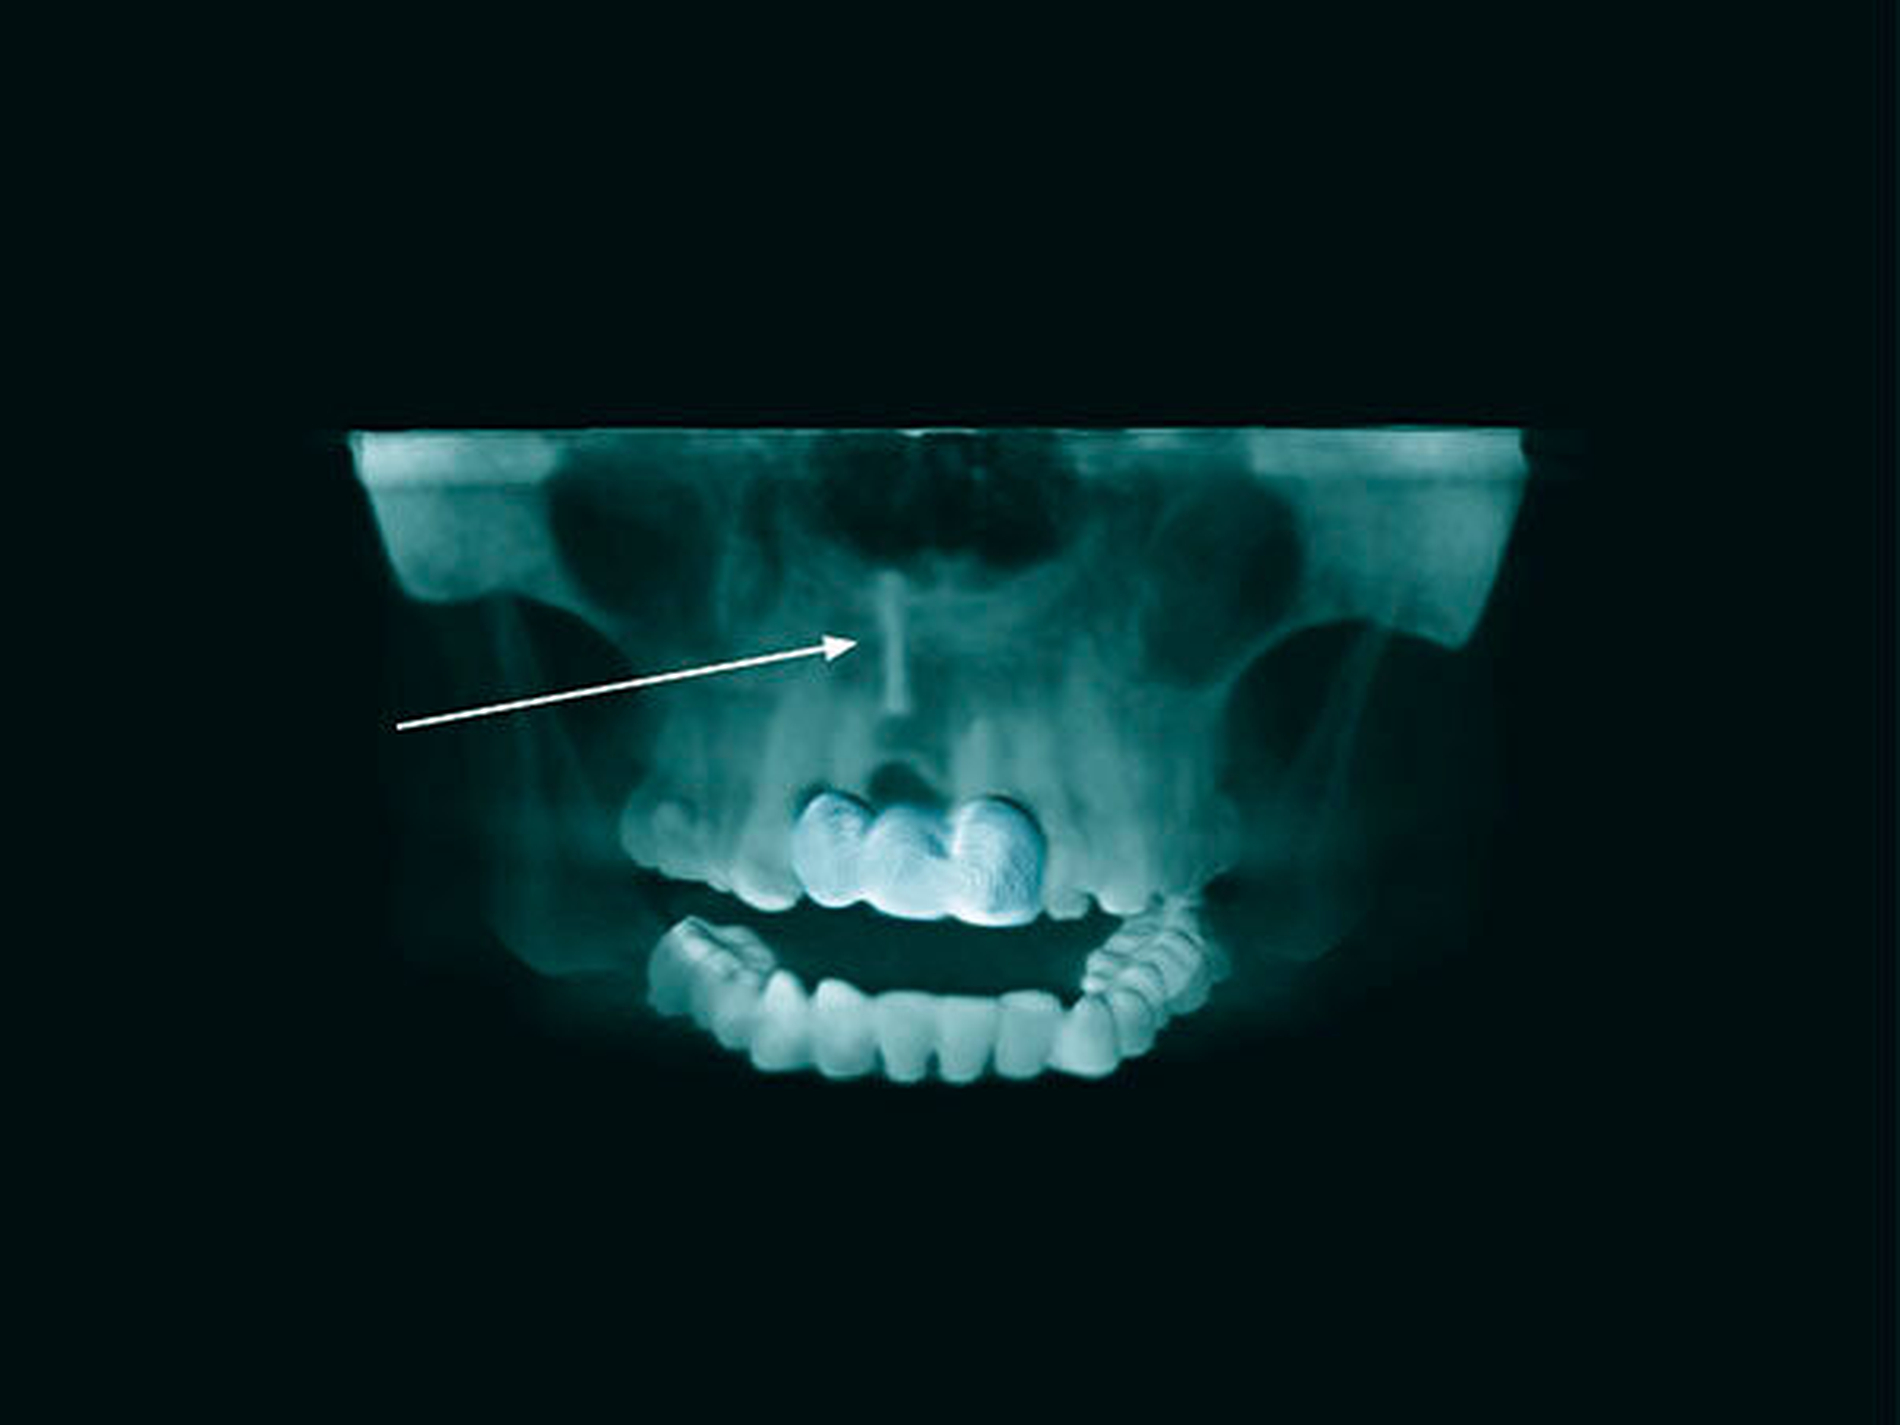

Eine 48-jährige Frau stellte sich in unserer Abteilung vor, nachdem ihr Zahnarzt im OPG einen Fremdkörper apikal der Alveole von Zahn 11 (Abbildung 1) diagnostiziert hatte. Das Röntgenbild wurde im Zuge einer angestrebten Implantatplanung in Regio 11 angefertigt. Bis dato war die Patientin mit einer Brücke von 12–21 in der Oberkieferfront versorgt, nachdem sie im Alter von neun Jahren Zahn 11 bei einem Sturz verloren hatte. Nach eigenen Angaben habe man damals versucht, den Zahn zu replantieren. Nach vorübergehendem Erfolg der Reinsertion des Zahns sei dieser nach einiger Zeit allerdings wieder verlustig gegangen. Es erfolgte die Versorgung mit einer provisorischen, später mit einer definitiven Brücke. Über den Vorgang der Replantation, die Verwendung eines Wurzelstifts oder den Verbleib des Stifts im Oberkiefer war der Patientin nichts bekannt. Im Zuge der Implantatplanung wurde ein DVT angefertigt, das den Verdacht eines Fremdkörpers, weit apikal der ursprünglichen Insertionslokalisation, bestätigte (Abbildungen 2 und 3).

Im vorliegenden Fall kam es nach retrograder, extraoraler Aufbereitung des Zahns und anschließender Stiftinsertion zur Ersatzresorption des Zahns mit Verbleib des Keramikstifts im Oberkieferknochen. Da die Patientin das Trauma im jungen Alter erlitt, unterlag die Maxilla in den folgenden Jahren dem physiologischen Knochenwachstum. Der verbliebene Stift folgte passiv dem Oberkieferwachstum und fand – mit dem kranialen Anteil – seine endgültige Lage im Bereich des Nasenbodens (Abbildung 6).